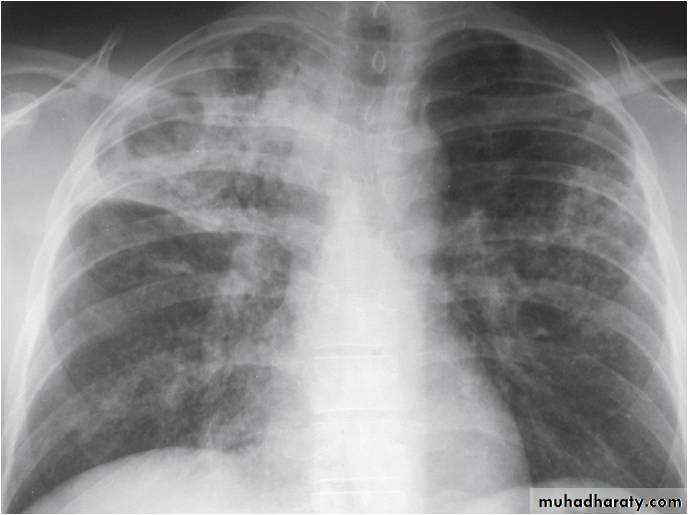

Post primary TB broncho pneumoniacotton wool sign

Post primary TB Bronch pneumonia

Q ???? Be careful in description & DxBoth of them have similar appearance of broncho pneumonic shadow

??????What is being the pit fall in such films ???

Who can you differentiate ???

60.post primary TB ( cotton wool appearance )

61.post primary TB notice upper apical Broncho pneumonic shadow

62.Q??? Film

63.Q assessment

64.answer this film of Broncho pneumonic (lobular pneumonia ) VS upper zone apical Broncho pneumonic shadow due to post primary TB